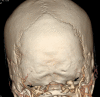

Objective The posterior condylar canals (PCCs), posterior condylar veins (PCVs), occipital foramen (OF), and occipital emissary vein (OEV) are potential anatomical landmarks for surgical approaches through the lateral foramen magnum. We performed the study to make morphometric and radiological analyses of the various emissary foramens and vein in the posterior cranial fossa. Methods Morphometric study were performed on 95 dry occipital bones and radiological analyses on computed tomography (CT) angiography images of 150 patients. The number of OFs on both sides was recorded and PCC length and mean diameters of the internal and external orifices of PCC were measured for bony specimens. Prevalence of PCV and PCV size was investigated using CT angiography. Results Mean PCC length was higher in the left side (9.85 ± 2.5). Mean diameter of the internal orifice and the external orifice diameter were almost the same. The majority of PCCs (75-79.33%) had 2 to 5 mm diameter; only 4 to 9.2% were small in size (< 2 mm). In CT angiography, PCV was not identified in 23 (15.33%) patients. PCVs were located bilaterally in 105 (70%) and unilaterally in 22 (20.5%) patients. Only 11.3% of PCVs were large in size (> 5 mm), 80% of PCVs were medium sized (2-5 mm), and 8.6% were small sized (< 2 mm). Conclusion Normal values of OF, PCC, PCV, and OEV could serve as a future reference for the understanding of the physiology of craniocervical venous drainage, which is necessary to avoid surgical complications and can also serve as a guide to surgical interventions for pathologies of the posterior cranial fossa, such as tumors and injuries.